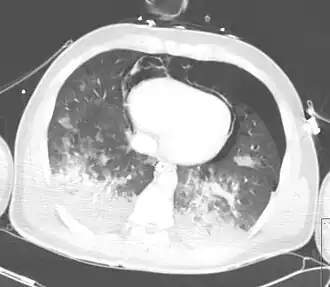

TAC mostrando neumopericardio con neumomediastino, neumotórax, hemotórax, y contusión pulmonar después de un severo traumatismo torácico | ||

Neumopericardio es una condición médica donde entra aire en la cavidad pericárdica. Esta condición ha sido reconocida en neonatos prematuros, en el que se asocia con patología pulmonar severa, después de una resucitación enérgica, o en la presencia de ventilación asistida.[1] Esta es una complicación seria, la cual si no se trata puede llevar a taponamiento cardiaco y la muerte. Una condición llamada neumomediastino la cual es la presencia de aire en el mediastino, puede imitar y también coexistir con neumopericardio.